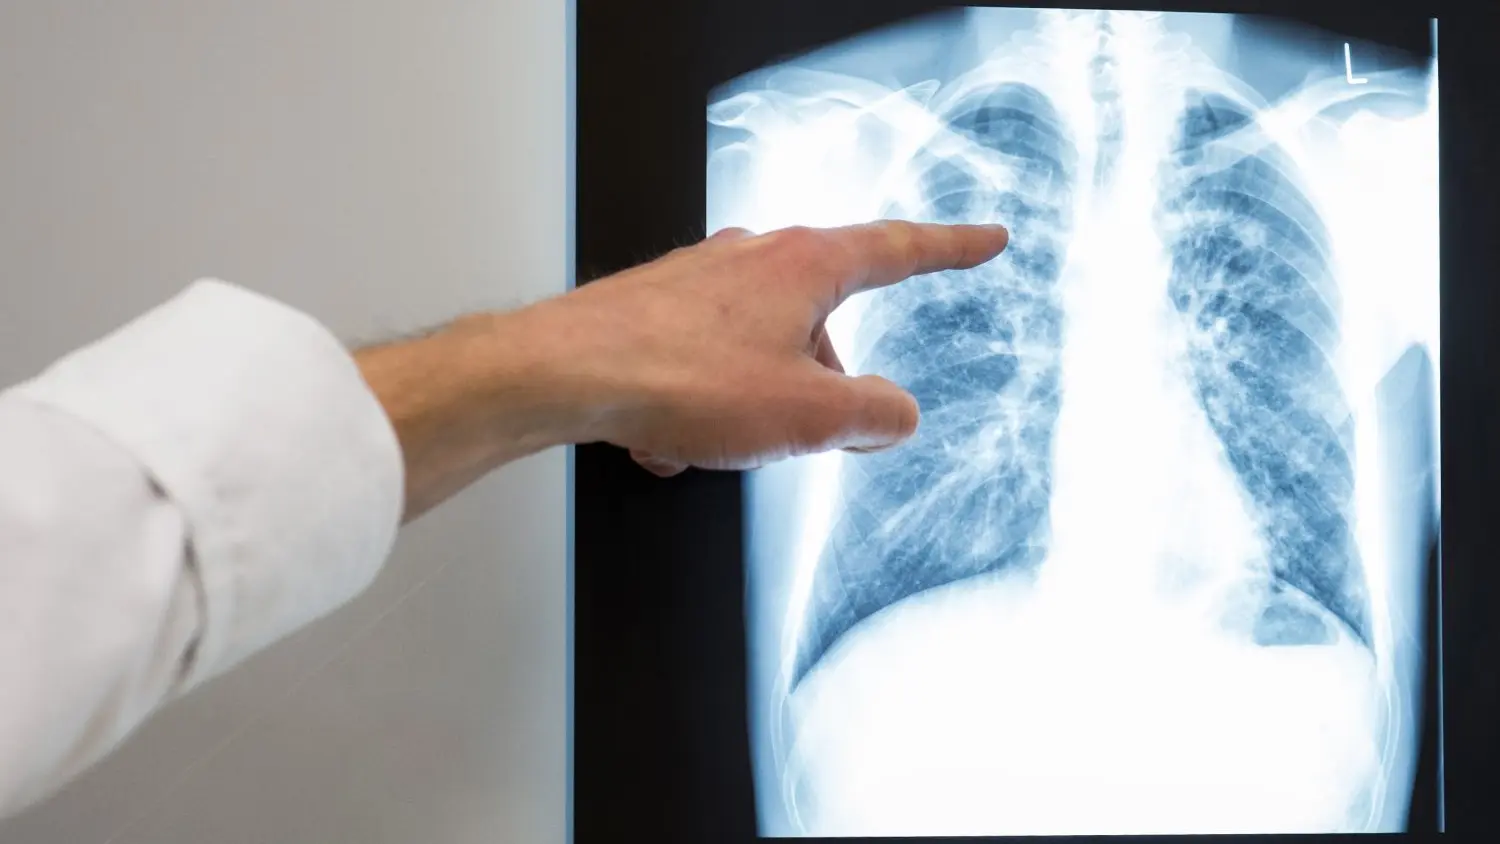

Ein Großteil der Erkrankten (70 Prozent) leidet dem RKI zufolge an einer Lungentuberkulose. Eine Infektion zeigt sich durch Husten, der in seltenen Fällen blutig sein kann. Gelegentlich kommt es zu Brustschmerzen und Atemnot. „Bei länger bestehendem Husten sollte auch an Tuberkulose gedacht und entsprechend den bestehenden Empfehlungen durch eine Röntgenuntersuchung der Lunge weiter untersucht werden“, empfahl RKI-Präsident Lars Schaade.